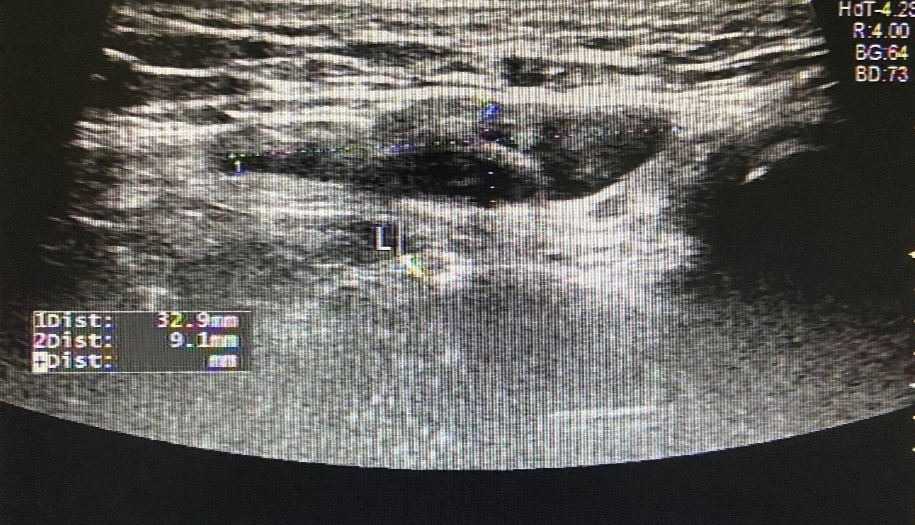

图 1 左侧腹股沟区包块

超声所见

左侧腹股沟区见范围约 4.4cm×3.2cm×2.0cm 无回声区,可见少量分隔,增减腹压大小无明显变化。右侧腹股沟区未见明显异常回声。

超声提示

左侧腹股沟无回声区,子宫圆韧带囊肿?积液?

术后证实为左侧子宫圆韧带囊肿。